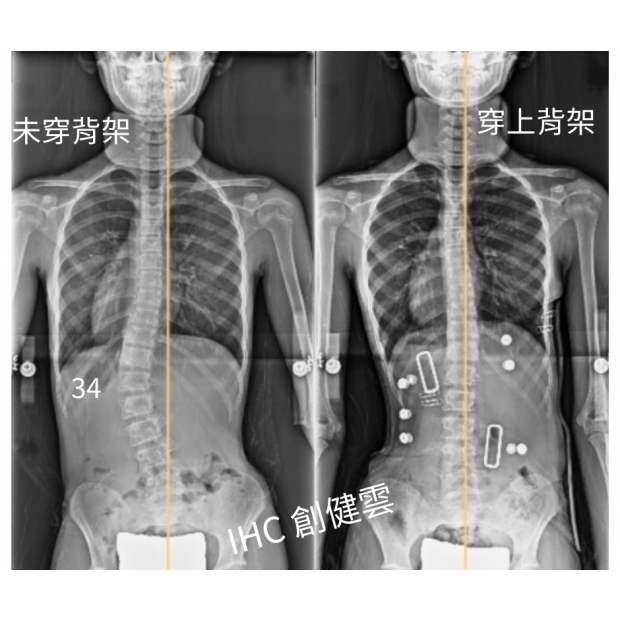

10歲脊椎側彎女孩,腰彎34度